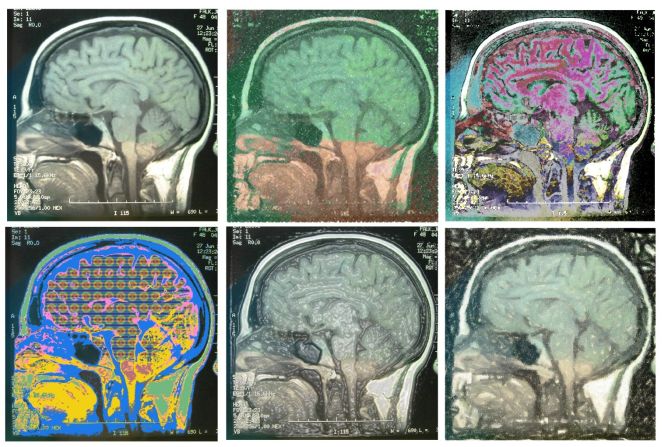

Novo istraživanje pokazalo je da uzimanje suplemenata vitamina E može da poveća rizik za pojavu krvarenja u mozgu

Pregled dosadašnjih istraživanja koja su sproveli naučnici jednog od najpoznatijih svetskih medicinskih fakulteta Harvard u Bostonu, pokazao je da ljudi koji uzimaju vitamin E u tabletama imaju 22 odsto veće šanse za hemoralgijski moždani udar.

Međutim, pokazalo se da vitamin E istovremeno za 10 odsto smanjuje rizik za ishemijski moždani udar, koji je ujedno i najčešći oblik moždanog udara. Iako treba biti oprezan, učinak vitamina E na rizik za moždani udar ipak je mali, jer od njega ima više koristi nego štete.

Istraživači su procenili da na svakih 1.000 ljudi koji se leče vitaminom E dolazi 0,8 odsto više hemoralgijskih moždanih udara i 2,1 odsto manje ishemijskih moždanih udara. Istraživači su pregledali podatke sakupljene u devet istraživanja u kojima je ukupno sudelovalo više od 118.000 ljudi.

Oko 85 odsto moždanih udara su ishemijski i nastaju kao posledica začepljenja neke od moždanih arterija, dok preostalih 15 odsto moždanih udara otpada na hemoralgijske koji nastaju kao posledica krvarenja u mozak.